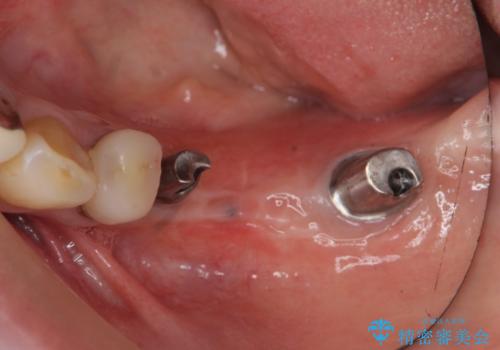

- 左下に長年使用した入れ歯が合わず、よりしっかりと噛みたいという希望で来院されました。

入れ歯をはずししっかりと噛む手段としてインプラント治療を進めていきます。

- 90万円(ストローマンインプラント×2・チタンカスタムアバットメント×2・ジルコニアクラウン×3)費用は治療当時の料金となります

インプラントを用いることで、たくさん失ってしまった奥歯を入れ歯よりもしっかりと噛む状態へと回復することができます。